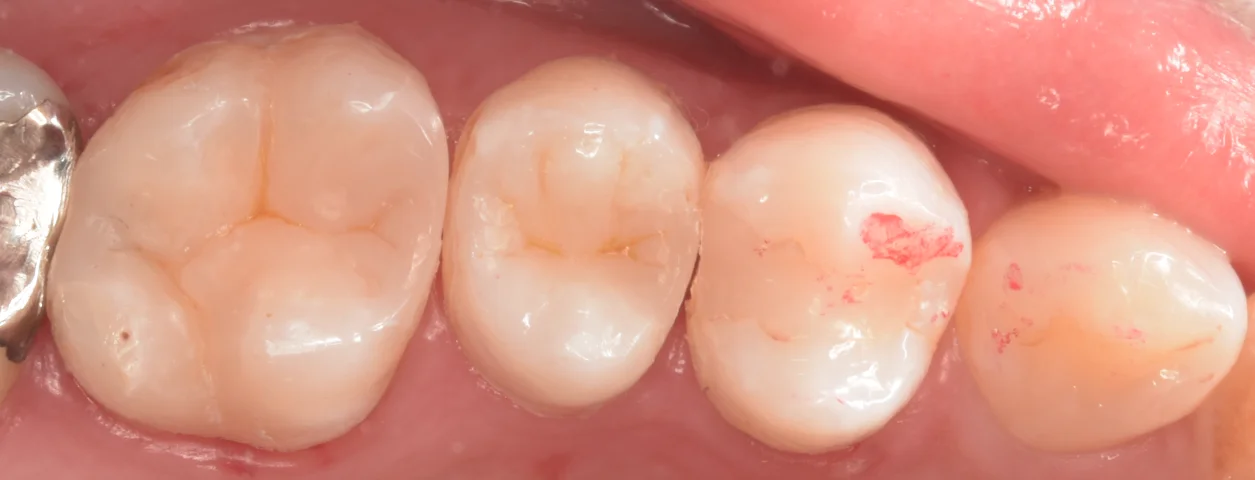

ラバーダム防湿を行っている状態で詰め終わった写真がこちらになります。

今回は右から2番目の歯は虫歯ではなかったので治療をしていませんが、元々入っている保険の詰め物の形態が不良なため、次虫歯になったらそこも修正する感じになると思います。

まだ詰めたところと歯の色のギャップがありますが・・・1週間程度すると歯の乾燥が落ち着き、違和感も消えてくるはずです。